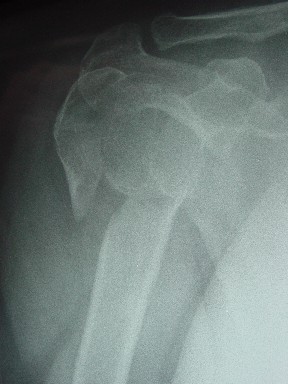

сделать закрытую репозицию с помощью ЭОПа совсем не сложно, после этого еще проще провести 3-6 спиц и получить красивую рентгенограмму. Есть только небольшая проблема это ROTATOR CUFF. Для плечевого сустава только костное восстановление не достаточно. для функции плечевого сустава нужны вращатели.

Давайте представим себе состояние манжетки вращателей после вывиха плеча, а еще и с отрывным переломом бугров. Головка может и прирастет, еесли не будет аваскулярного некроза, но хорошего функционального результата не ждите.

Висеть будет красиво. У людей физически активного периода жизни нужно открыть, восстановить костную анатомию и восстановить сухожильный аппарат.